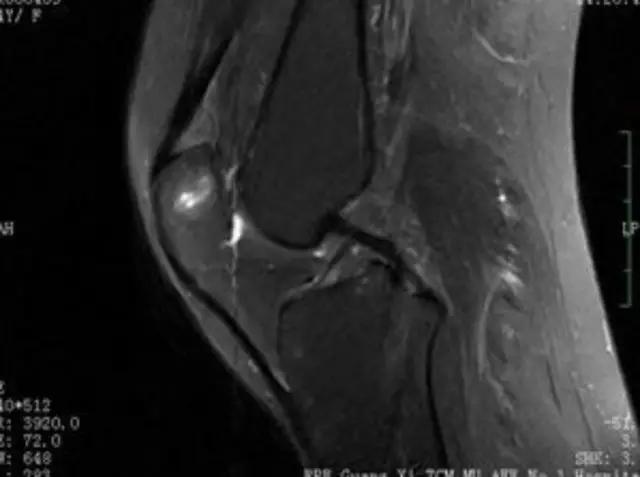

下图是同一个病人的MRI照片,MRI显示的内容更多,包括骨与软组织等,很多早期的、细微的病变都能清晰显示,其诊断报告对病人造成的影响也更大!

地中海贫血与白血病均为血液系统的问题,主要表现在骨髓,疾病的发病机理有别,MRI表现也不相同;我们可能不是很熟悉这些疾病,也能够从MRI发现区别。图1:正常膝关节 图2:地中海贫血 图3:白血病

我们可能都不熟悉T1、T2,怎么办?当我们发现有问题后,利用照片上图像的对比,推测病变的可能也是一种诊断方法。病例:黄XX,女,39岁,左膝关节反复交锁1年。图1:肿物信号与骨信号一样图2:肿物信号与骨信号一样图3:肿物信号与骨信号不一样 肿物应该与骨相关,但不是骨性,推断:膝关节滑膜软骨瘤。手术后得到证实。